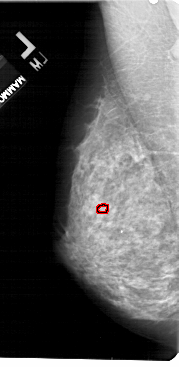

A_1755_1.LEFT_CC

LEFT_CC LINES 5236 PIXELS_PER_LINE 2506 BITS_PER_PIXEL 12 RESOLUTION 43.5 OVERLAY

FILE: A_1755_1.LEFT_CC.OVERLAY

TOTAL_ABNORMALITIES 1

ABNORMALITY 1

LESION_TYPE CALCIFICATION TYPE PLEOMORPHIC DISTRIBUTION CLUSTERED

ASSESSMENT 4

SUBTLETY 1

PATHOLOGY BENIGN

TOTAL_OUTLINES 1

BOUNDARY